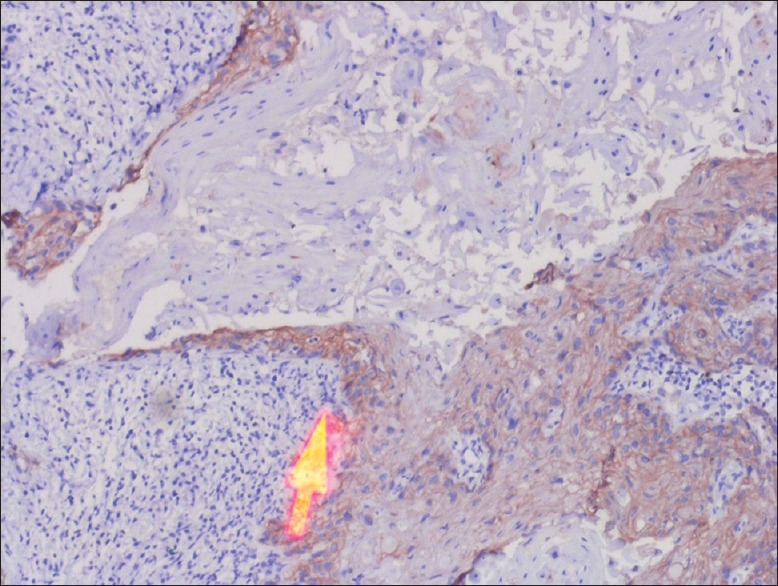

Materials and methods: A total of 50 archival lymph node blocks, both positive and negative neck nodes of the patients treated for OSCC, were used for the assessment of DSG1 and 3 expressions by immunohistochemistry (IHC) following their histopathological examination. The assessment of IHC staining was conducted by two independent maxillofacial pathologists as per the grading criteria in all the lymph node sections.

Results: A total number of 88 nodes were assessed, of which 27 were positive on histopathological assessment. DSG1 and DSG3 positivity were noted and varied between 11.4-12.5% and between 20.5-22.7% of positive nodes, respectively, between the observers. Cronbach's alpha was calculated for interobserver reliability for positive identification of metastatic lymph nodes. Area under curve (AUC) values for DSG1 were 0.478 and 0.02 for DSG3, and not so statistically significant value for DSG1 was obtained (P > 0.05) compared to DSG3 (P = 0.000).

Conclusion: Current study results do not confirm the roles of DSG1 and 3 as potential markers for occult lymph node metastasis, and hence, the reliability of their roles may require further studies along with other markers of lymph node metastasis. Even though overexpression of DSG3 and partial expression of DSG1 in OSCC is seen, further studies may be required to confirm them either as a diagnostic or prognostic marker which can be useful for future management in cases of radical neck dissections.